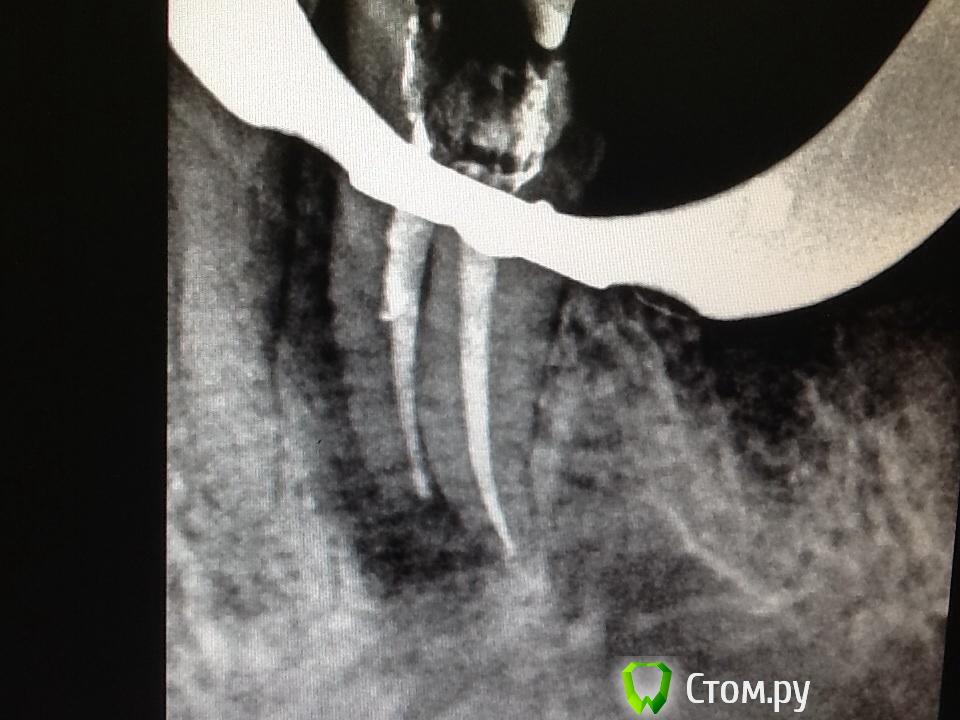

Л Ю С Я Опубликовано 29 мая, 2014 Поделиться Опубликовано 29 мая, 2014 Люся,ждём кейс ; )Закончили лечение зуба 35. Я, конечно , не умею красиво пиариться . Вот что есть, ситуация до лечения, обострениеС вкладкой возилась около часа, думала умру на ней. Зато в каналы провалилась. Снимок сразу в этот же деньПотом еще посещение на сл день, каналы домыла, кальций плотнее. Вытащили обломыш из перешейка. Закончили через 10 дней. Пока бломба из композита, поехали в отпуск 2 Ссылка на комментарий

Аслан Опубликовано 29 мая, 2014 Автор Поделиться Опубликовано 29 мая, 2014 Люся, это точно 35? Больше похож на 15...Вы Молодец. Маленькое пожелание. Надо было сделать снимок светлее, чтобы видеть границу кости по гребню.Я так понимаю в этом зубе нет феррула? Ортопед видел зуб после извлечения вкладки? Ссылка на комментарий

Л Ю С Я Опубликовано 29 мая, 2014 Поделиться Опубликовано 29 мая, 2014 Люся, это точно 35? Больше похож на 15...Вы Молодец. Маленькое пожелание. Надо было сделать снимок светлее, чтобы видеть границу кости по гребню.Я так понимаю в этом зубе нет феррула? Ортопед видел зуб после извлечения вкладки?Не ну какой 15, 35 точно.)))) Феррул как ни странно есть. Что будем с ним делать потом не решили. Работа из серии гарантия 1 день. Меня больше волнует нет ли где трещины, в бинокулярах ведь не все видно. Одиночных карманов вроде нет. Маркером не прокрашивается. Ссылка на комментарий